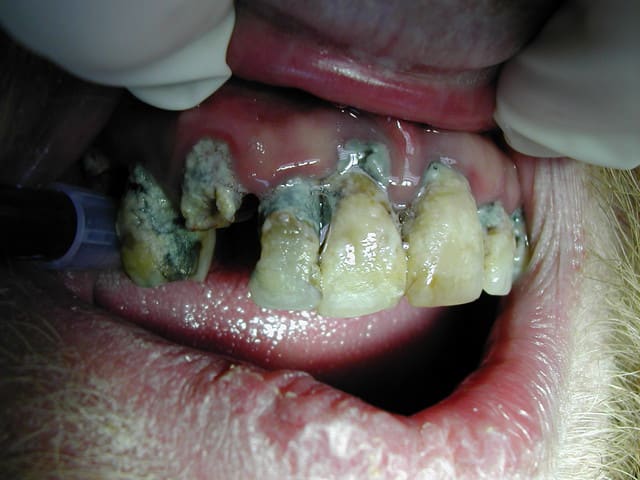

Tout nouveau de ce matin , mais pas glop ! 34 ans mâle célibataire , à du psoriasis ...a décidé de se prendre en main .